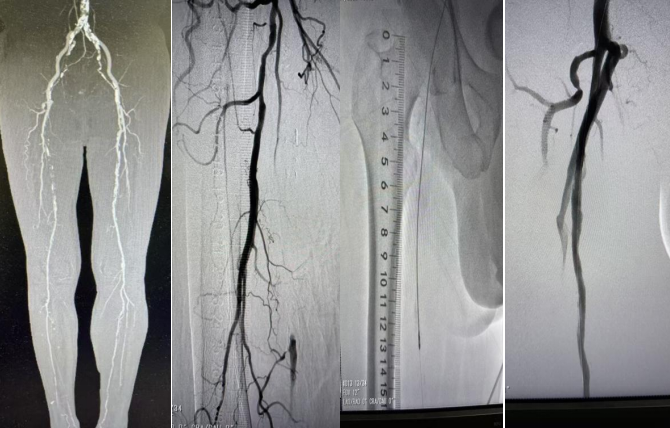

本例患者为老年男性,右足疼痛伴皮肤破溃2月,入院行CTA检查提示右侧股浅动脉长约23cm硬化闭塞。因右下肢缺血症状明显,如不及时处理存在肢体缺血坏死截肢风险,手术指征明确。术前在张瑞鹏主任指导下,医务人员积极完善相关术前检查,并组织了多次科内术前讨论,对手术方式、术中术后的风险及并发症等均制定了详细计划及预案,确保手术安全、顺利进行。本例手术难点在于患者动脉钙化严重,且闭塞管腔继发大量血栓,传统的减容设备难以同时处理钙化斑块及腔内血栓,不能很好地满足临床需要。经详细评估患者病情及征得患者及家属同意后,决定选用Jetstream血管斑块旋切导管减容设备,最终顺利完成手术。

外周动脉疾病患病率高、致残率高且死亡率高,虽然目前介入手术已经逐渐开展,但因患者血管钙化严重、管腔内容物复杂,单纯球囊扩张结合载药器械的远期通畅率仍未达到患者需求,患者常需一年后再次手术,经济压力大。Jetstream血管斑块旋切导管作为一款可以同时处理血栓、斑块及钙化的减容导管,可以有效旋切并抽吸下肢血管的腔内容物,为载药器械提供更加优秀的管腔,为患者提供更长期的通畅。与同类腔内减容方案相比,操作更加简便,无需在术中将导管拿出体外进行,节省手术时间。一根导管即可处理包括血栓、斑块钙化在内的血管内容物,节约手术费用,使用前可以不使用小球囊预扩,更加节省手术费用,且器械自带差异化切割功能,更安全。